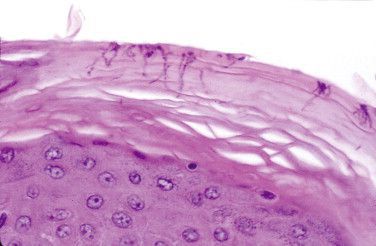

Вместе со слизистой оболочка образует первую линию защиты от инфекций. Кератинизация (отмирание и ороговение клеток эпидермиса) и сухость ограничивают размножение микроорганизмов, которое поддерживается за счет низкого pH на поверхности кожи и ограничивает колонизацию кожи комменсалами (микроорганизмами, которые в норме живут с человеком, получают пользу от это и не наносит урона). Микроорганизмы должны преодолевать эти защитные механизмы, проникая в интактный эпидермис, либо растворяя клетки кератиноцитов, либо они могут проникать через механические микротравмы кожи.

Роговой слой кожи состоит в основном из кератина, смешанного с секретируемыми липидами придатков кожи, которые используются в качестве субстрата для метаболизма бактерий, паразитирующих на коже .

При повышении уровня липидов начинается активное размножение комменсалов, что приводит к воспалительному процессу. Эритразма – одно из заболеваний, которое в большинстве случаев возникает в складках кожи, где на теле человека наибольшая концентрация секреторных желез .

В результате таких предрасполагающих факторов, как высокая температура, влажность в результате мацерации кожи, коринебактерии проникают в верхнюю треть рогового слоя, где интенсивно размножаются. Имеет значение несоблюдение правил личной гигиены, состояние иммунной системы и наличие сопутствующих заболеваний, таких как сахарный диабет, гипертиреоз, ожирение. Бактерии проникают в межклеточные пространства и внутрь клеток, растворяют фибрил-кератин и вызывают утолщение рогового слоя .